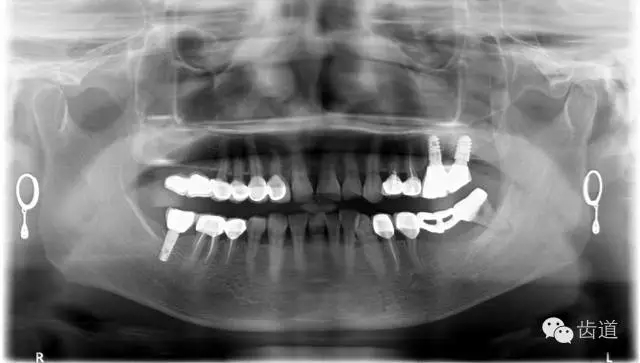

1、術(shù)前全景片

2、45,46術(shù)前片顯示根管上段充填物,根管影像不清晰,少許根尖暗影

3、34術(shù)前片顯示遠(yuǎn)中面暗影近髓

4、 全景片